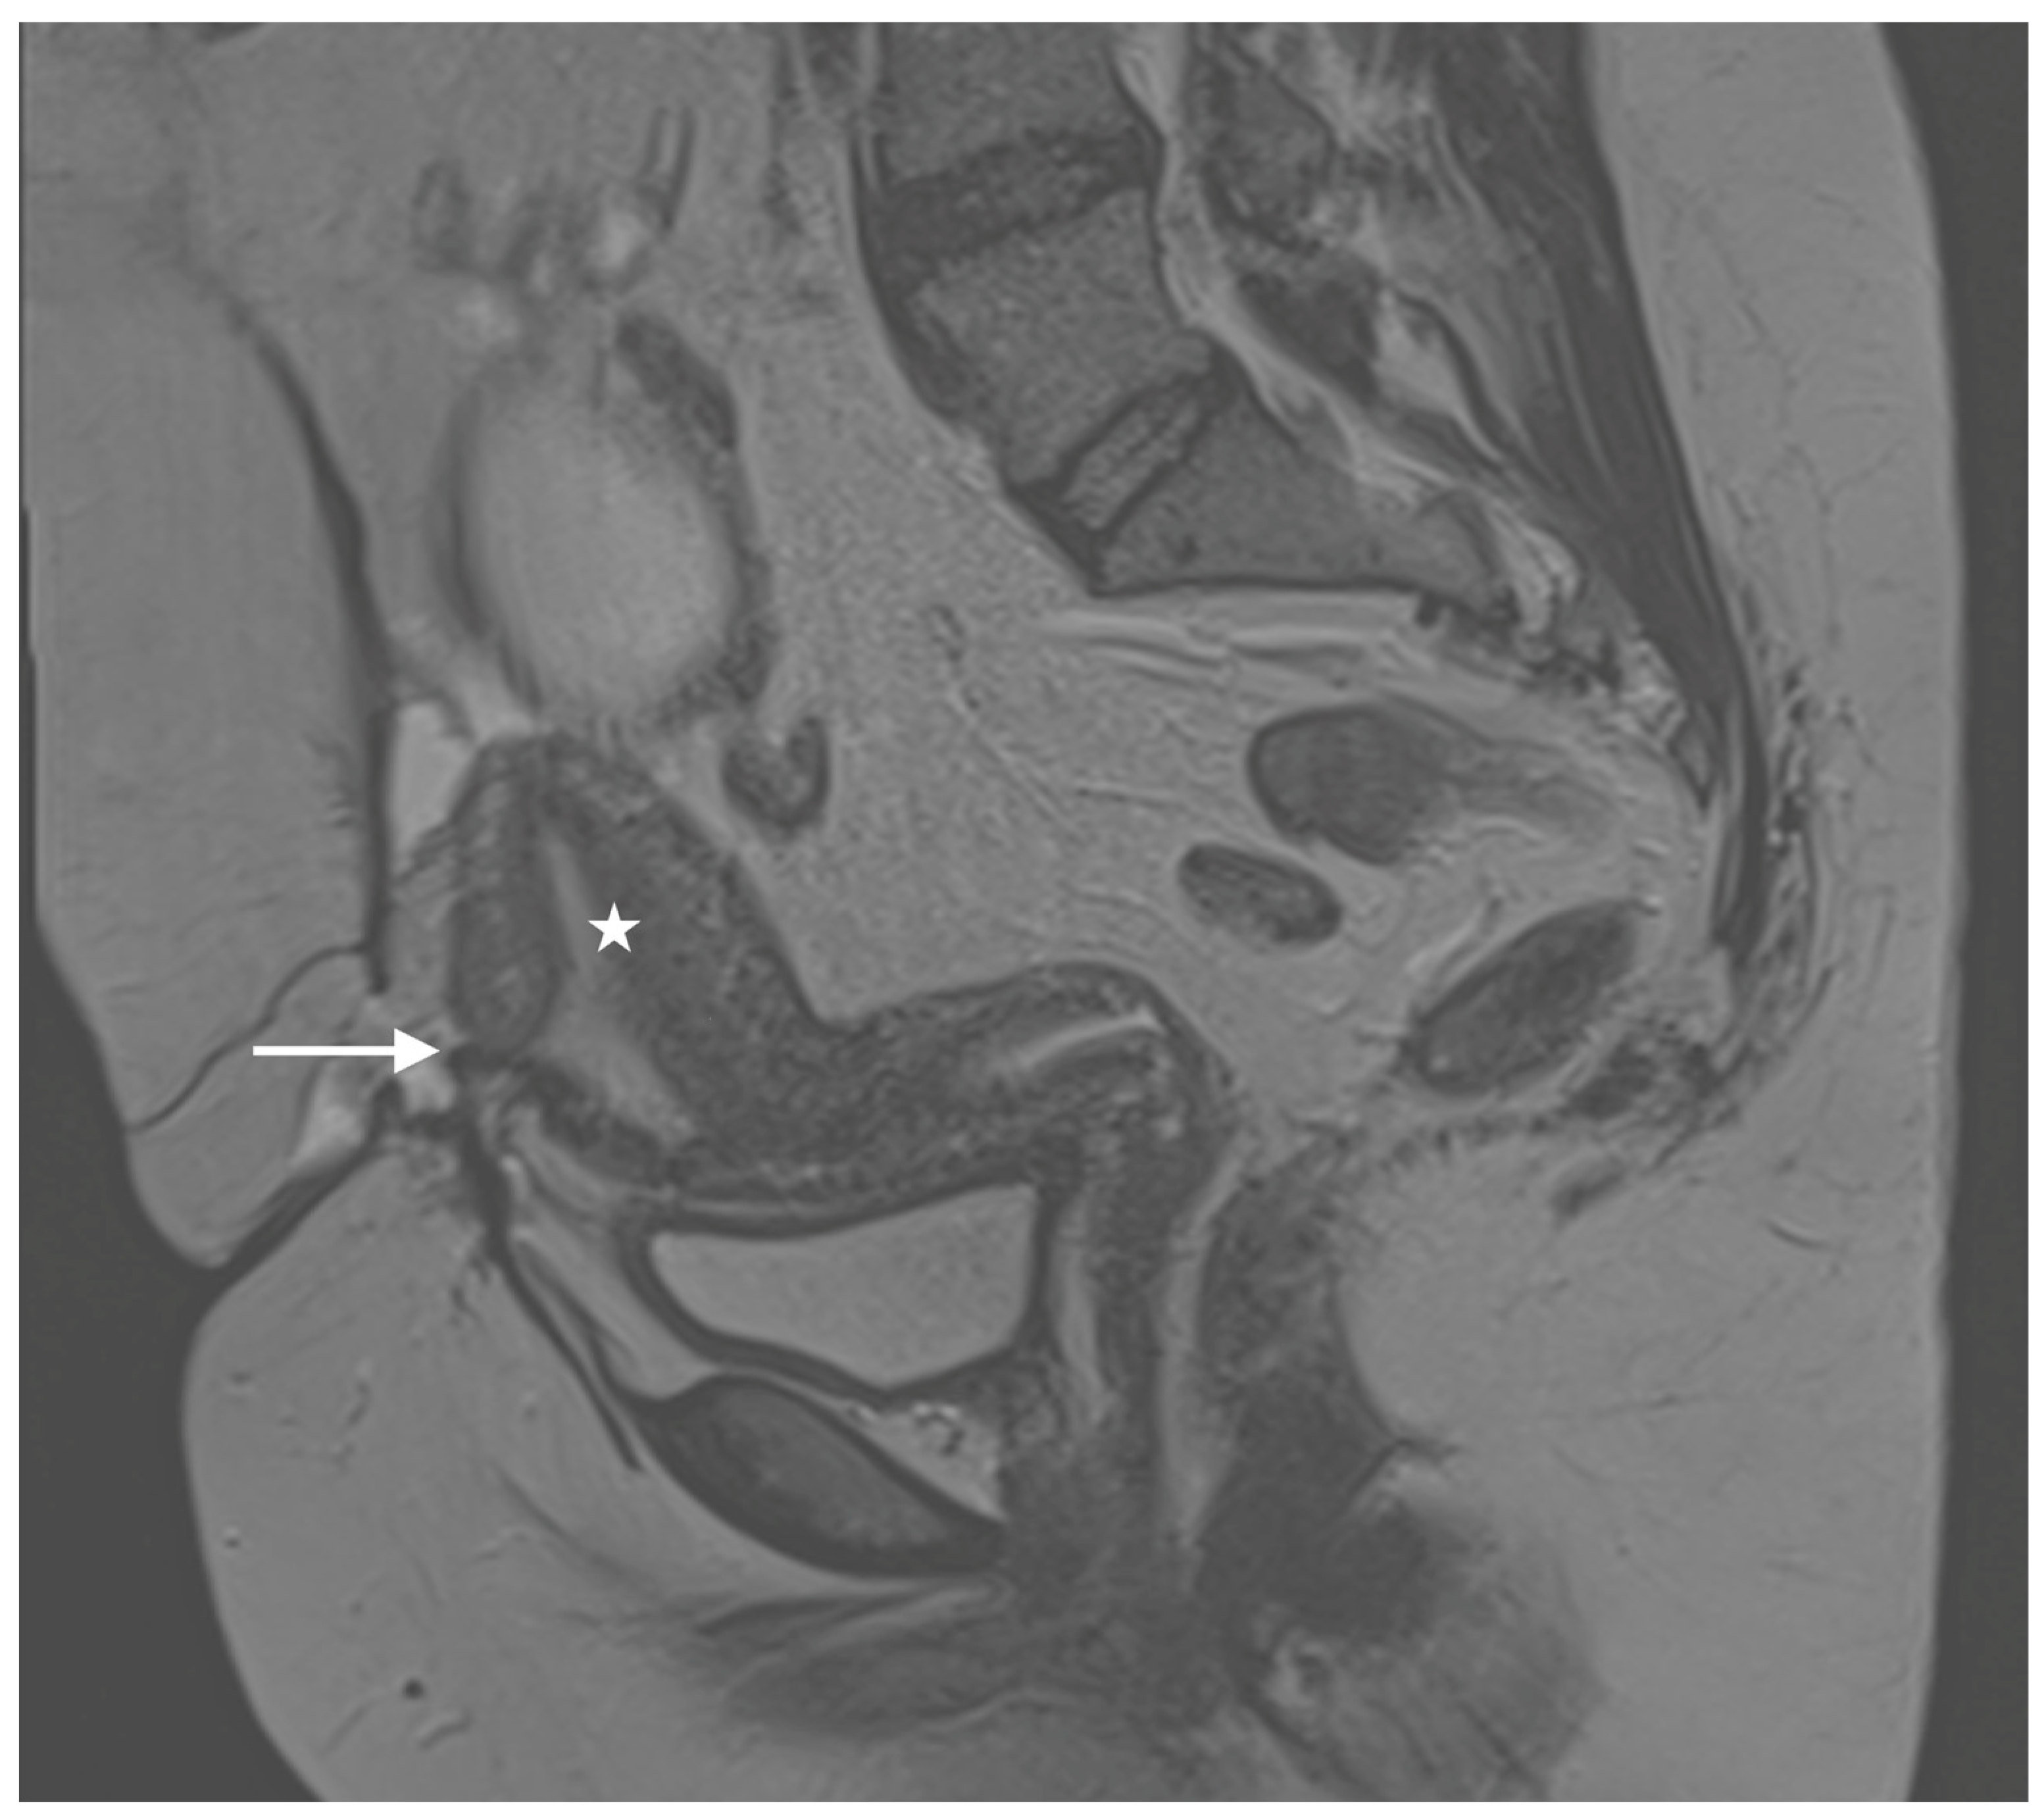

Six months later, the patient returned to our clinic, reporting cyclic pain and catamenial bleeding from the area of the persistent wound dehiscence during menstruation. Up to this point, dysmenorrhea, dyspareunia, chronic pelvic pain or other endometriosis-related symptoms had not been reported, nor had any preceding abdominal surgery revealed signs of endometriosis. Our clinical examination raised suspicion of a fistulous tract between the abdominal wall and the anterior wall of the uterus in the midline of the cesarean scar. This suspicion was further supported by magnetic resonance imaging (MRI) of the abdomen, which suggested a distinct contact area between the uterus and the abdominal wall (Figure 1), along with impaired wound healing and fascial dehiscence in the context of the previous cesarean section.

Figure 1.

Diagnostic imaging (MRI, T2) shows a scar region (arrow) within the ventral corpus uteri. The corpus uteri (asterisk) is displaced ventrally towards the abdominal wall. In alignment with the clinical symptoms, the findings are highly suspicious for fistula formation.